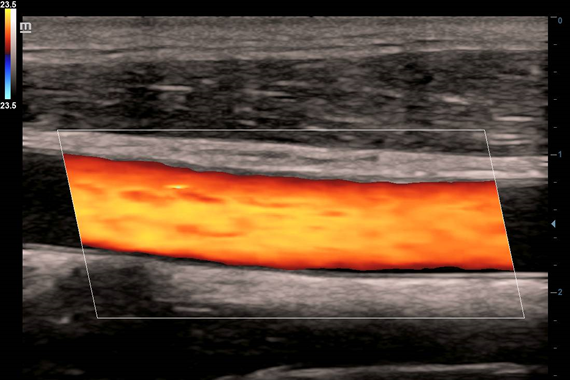

Клинические изображения

- Цветной допплер (Color Doppler)

- Цветной допплер (Color Doppler)

- Ангиология

- iScape™ View - панорамное сканирование – отображение на экране объектов большой протяженности (одновременное отображение на экране крупных объемных образований, структур и органов на большом протяжении и т.д.) с возможностью проведения расчетов и измерений.

- Auto IMT Package - измерения и анализ толщины комплекса интимамедии (КИМ) сонной артерии.